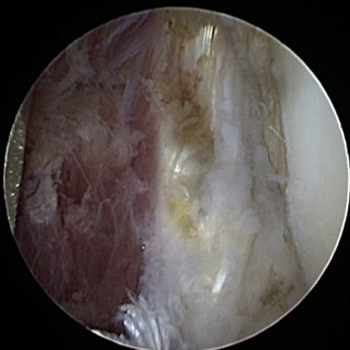

관절내시경 수술 전

관절내시경 수술 후

ㆍ환자 동의를 받은 자료이며, 이미지 사진은 실물과 다를 수 있습니다.

ㆍ16.07.12 관절내시경 당일 전, 후 사진입니다.